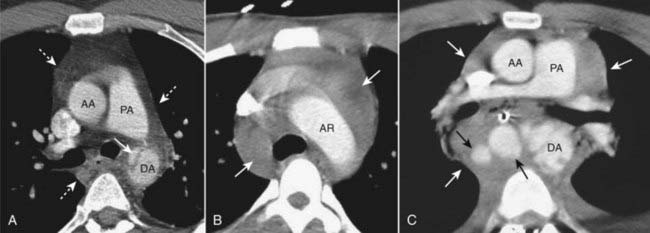

image

Figure 17-6 Aortic trauma, three different patients.

A, There is a tear at the level of the aortic isthmus represented by the lucent defect in the wall of the descending aorta (solid white arrow). A mediastinal hematoma is also present (dotted white arrows). B, There is a large mediastinal hematoma (solid white arrows). C, There are periaortic hematomas containing extravasated blood (solid black arrows) and a large mediastinal hematoma (solid white arrows). (AA = ascending aorta; AR = aortic arch; DA = descending aorta; PA = pulmonary artery.)